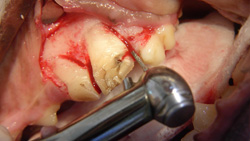

A full thickness mucoperiosteal gingival flap is planned (indicated by the dotted line). Important surgical anatomy includes the parotid and zygomatic salivary ducts at the distal (caudal) aspect of the affected tooth and the infraorbital neurovascular bundle, which is mesial (rostral) to the vertical incision location.

Step 2

The vertical incision is made starting 5 mm apical to the mucogingival line at the mesial aspect of the left maxillary 4th premolar tooth, with firm pressure along the mesial aspect of the alveolar juga of the mesiobuccal root, and continues ventrally to the gingival attachment at the crown. The incision is then extended horizontally within the gingival sulcus, deep enough to reach the alveolar crestal bone, and along the buccal surface of the tooth to the distal aspect of the maxillary 4th premolar. If more surgical exposure of the buccal bone (over the distal root) is needed, the incision can be extended to the distobuccal line angle of the maxillary 1st molar (as is depicted in this and the following steps).5-7 In addition, the remaining epithelial attachment is also incised circumferentially around the maxillary 4th premolar.

Step 3

A #4 Molt periosteal elevator is used to reflect the full thickness mucoperiosteal flap and expose the buccal alveolar bone. This reflection can stop at the mesiobuccal line angle of the maxillary 1st molar (just caudal to the tooth being extracted) or, if needed, it can continue over the buccal aspect of the maxillary 1st molar to the distobuccal line angle. The result will be a triangular gingival flap that should be well suited for coverage of the triangular defect created when the tooth roots are extracted.

Step 4

The buccal alveolar bone is removed using a round ball bur (#2, surgical length, friction grip) in a water-cooled, high-speed handpiece. The amount removed will depend on the experience and skill of the operator, but removing the alveolar bone to expose 25% to 50% of the buccal root surface should suffice. The removal of alveolar bone is guided by palpation and visualization of the alveolar juga of each root.